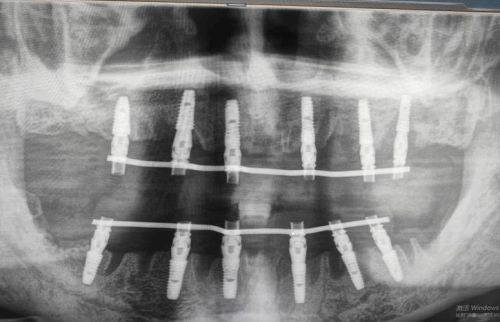

患者李先生 全口无牙颌种植修复

“我全口缺牙快五年了,吃饭都只能吃流食,生活特别不方便,陈医生给我做了无牙颌种植修复,他全程耐心讲解每一个治疗步骤,缓解了我的紧张情绪,术后没过多久就能正常吃饭了,现在终于能吃我爱吃的红烧肉了,陈医生的技术真的没得说。”